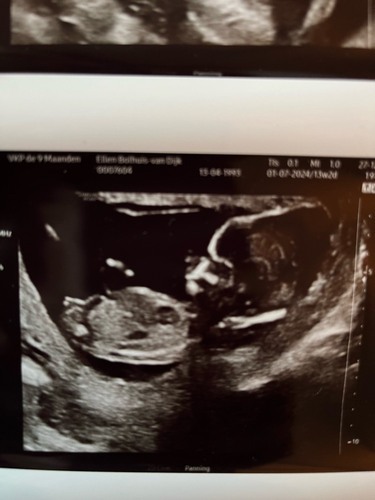

Wat denken jullie. Een meisje of een jongetje in juli? Echo is 13+2 dagen � ...

Ik neig naar een jongen!